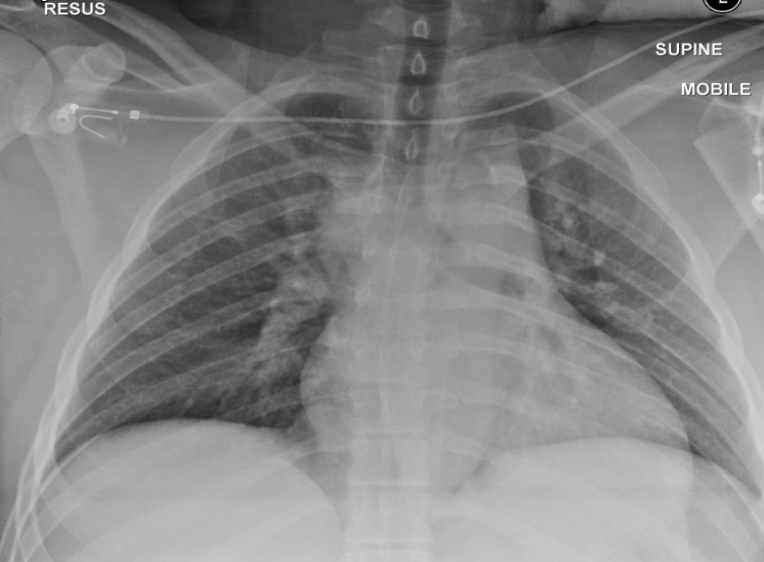

AP chest X-ray (critically ill patient and intubated)

tracheal intubation (above the carnia. if lower it will inter right main stem bronchous→leads ti left lung collaps)

NG tube

Central line (into SVC)

left main stem bronchous showing radio-opacity and patent bronchioles→Air broncho-grams (if localised→indicates infectious process)

Bilateral diffuse lung opacities on both lung fields (slightly more on left side)

Ddx: ARDs, decomensated heart failure, aspiration

Air bronchograms